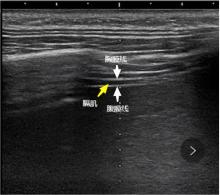

目的 研究在小儿腹腔镜腹股沟疝手术麻醉过程中,使用膈肌超声指导喉罩拔除时机的可行性和安全性。 方法 选取腹腔镜腹股沟疝修补手术患儿140例,随机将患儿分为膈肌超声指导拔除喉罩组(D组)和清醒拔除喉罩组(A组),两组患儿分别按照不同方式指导喉罩的拔除时机,比较两组患儿喉罩拔除过程中及拔除后出现咳嗽、拔除困难、喉痉挛、支气管痉挛、咽痛等呼吸不良事件的发生率,分析比较两组患儿外周血氧饱和度下降的发生率及处理方式。 结果 D组患儿拔除困难和喉痉挛的发生率均低于A组患儿,差异有统计学意义(P < 0.05),D组患儿发生呼吸不良事件的病例数少于A组患儿,差异有统计学意义(P < 0.05)。D组患儿拔除喉罩后血氧饱和度下降的发生率低于A组患儿,差异有统计学意义(P < 0.05)。D组患儿手术结束至拔除喉罩时间及Steward苏醒评分达4分时间均短于A组患儿,差异有统计学意义(P < 0.05)。 结论 在小儿腹腔镜腹股沟疝手术麻醉苏醒过程中,采用超声监测膈肌厚度变化率的方式可以更好地指导拔除喉罩,安全性更高。

Objective To investigate the feasibility and safety of using diaphragmatic ultrasound to guide timing of laryngeal mask extraction during anaesthesia for laparoscopic inguinal hernia surgery in children. Methods A total of 140 children undergoing laparoscopic inguinal hernia repair surgery were selected, and the children were randomly divided into two groups: the group with laryngeal mask extraction guided by diaphragmatic ultrasound (Group D) and the group with laryngeal mask extraction guided by awake (group A). The two groups were instructed on the timing of laryngeal mask extraction according to different ways, and the incidence of adverse events, such as difficulty in pulling out, cough, laryngospasm, bronchospasm, and pharyngeal pain, were compared between the two groups during and after the extraction, the analysis compared the incidence and management of peripheral oxygen desaturation between the two groups. Results The rates of difficulty in pullout and laryngospasm in group D were both lower than those in group A, and the number of cases of adverse events in group D was lower than that in group A, the difference was statistically significant. The incidence of oxygen desaturation after removal of the laryngeal mask was lower in group D than in group A, and the difference was statistically significant.The time from the end of surgery to removal of the laryngeal mask and the steward awakening score up to 4 points in group D were shorter than those in group A, and the differences were statistically significant. Conclusion During awakening from anaesthesia for laparoscopic inguinal hernia surgery in children, monitoring the rate of change in diaphragmatic thickness with ultrasound can lead to better guidance in the extraction of laryngeal mask with a lower incidence of adverse effects and greater safety.